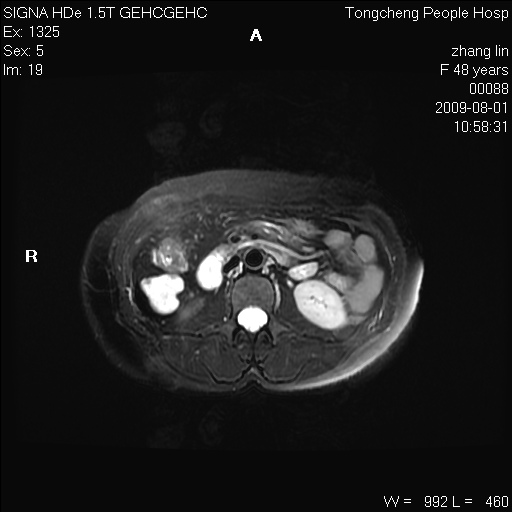

女,48岁。健康体检,彩超发现右肾占位性病变。平素健康。

临床诊断:右肾占位性病变,性质待定(囊肿?肿瘤?)。

上中腹部mr平扫+增强扫描,图像如下:

右肾上极见一类圆形病灶,t1wi呈等信号t2wi呈等高混杂信号,三期增强无强化,边界清---考虑囊肿出血。

同反相位均表现为等信号,病变无强化,考虑含蛋白的囊肿可能,弥散加权相或许有些帮助,